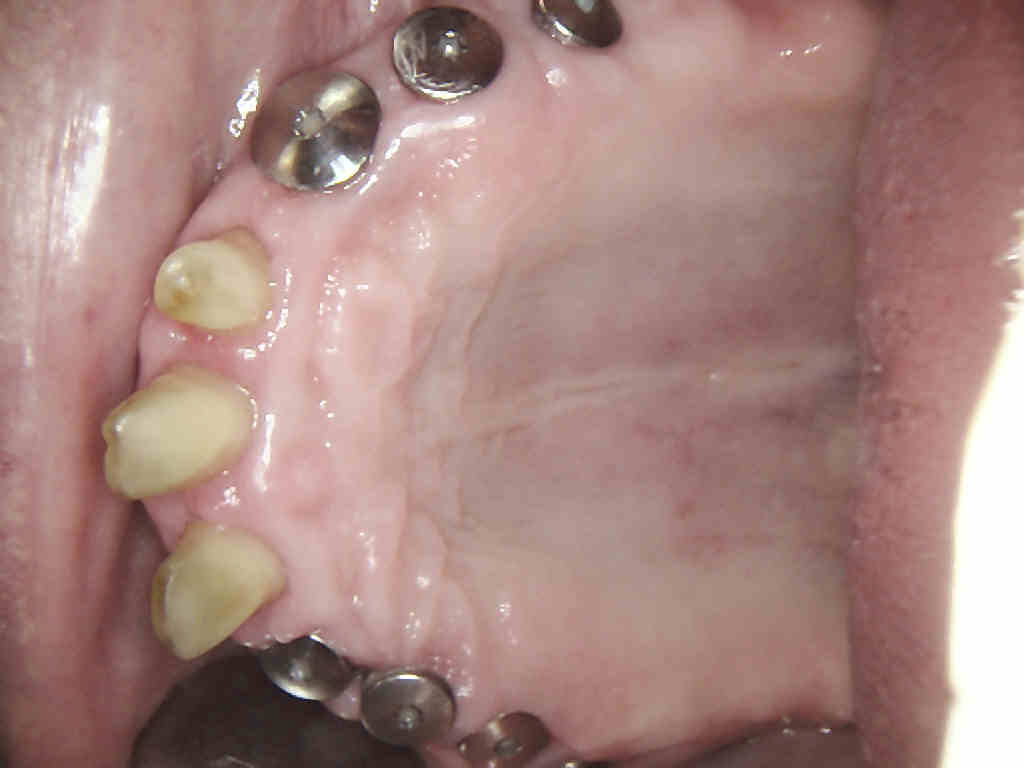

Dieser Zahnersatz wird individuell hergestellt und erfordert oft eine erhebliche Vorplanung in Zusammenarbeit mit dem Patienten und dem zahntechnischen Labor, um die für den Einzelfall beste Lösung zu erarbeiten, die sowohl die funktionelle Wiederherstellung der Funktion des Gebisses als auch die kosmetische Rehabilitation gewährt.

Oftmals kommt es vor, dass ein Zahn durch Karies, Frakturen, ausgedehnte Defekte oder übermäßige Abnutzung so zerstört ist, dass eine Wiederherstellung mit einer Füllung nicht mehr möglich ist.